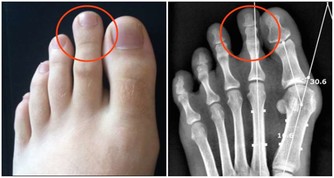

牙弓擴張。圖/wikipedia